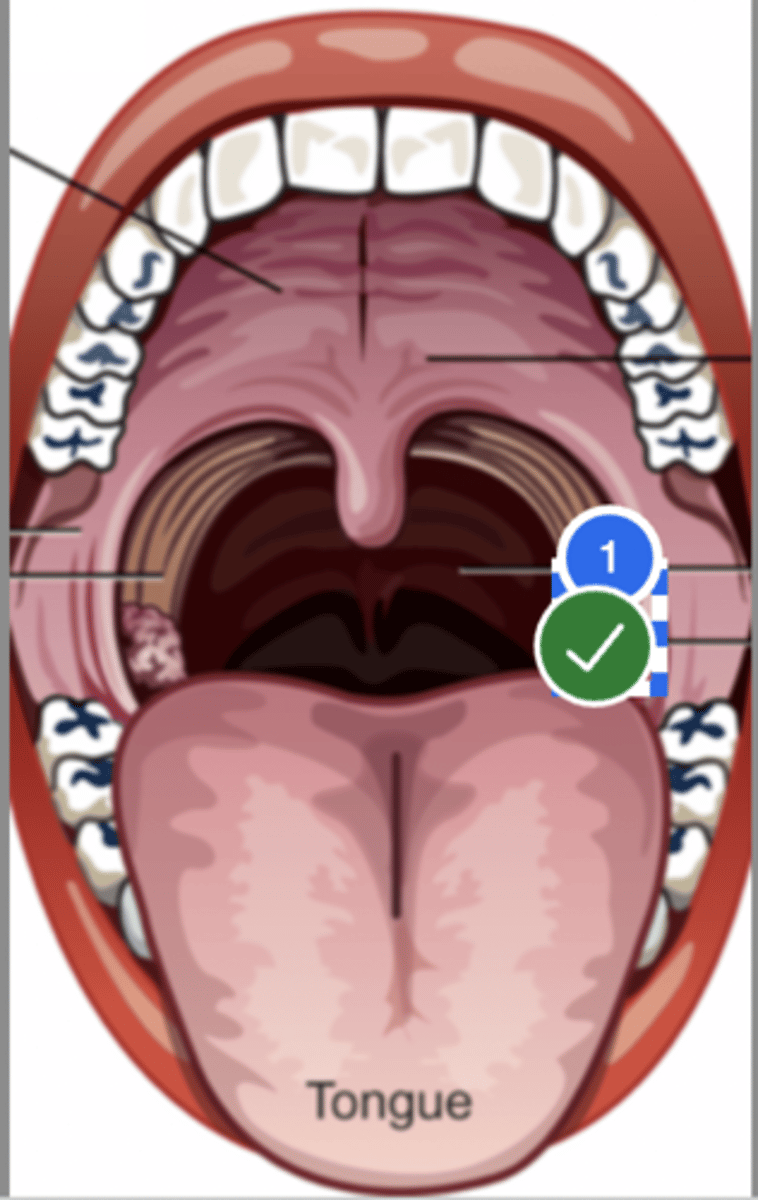

Label Right Anterior Faucial Pillar (superior view)

Label uvula (superior view)

Label palatine tonsil (superior view)

Label left true vocal fold (superior view)

Label right false vocal fold (superior view)

label right arytenoid (superior view)

Label trachea (superior view)

Label epiglottis (superior view)

Label left aryepiglottic fold (superior view)

Label laryngral surface of epiglottis (superior view)

Label lingual surface of epiglottis (superior view)

Label base of tongue (superior view)

Label right pyriform sinus (superior view)

Label upper esophageal sphincter (superior view)

Label right true vf (superior view)